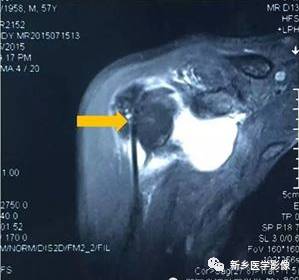

病例九:

红色箭头:冈上肌腱损伤

黄色箭头:二头肌腱长头腱脱位

蓝色箭头:肩胛下肌腱损伤